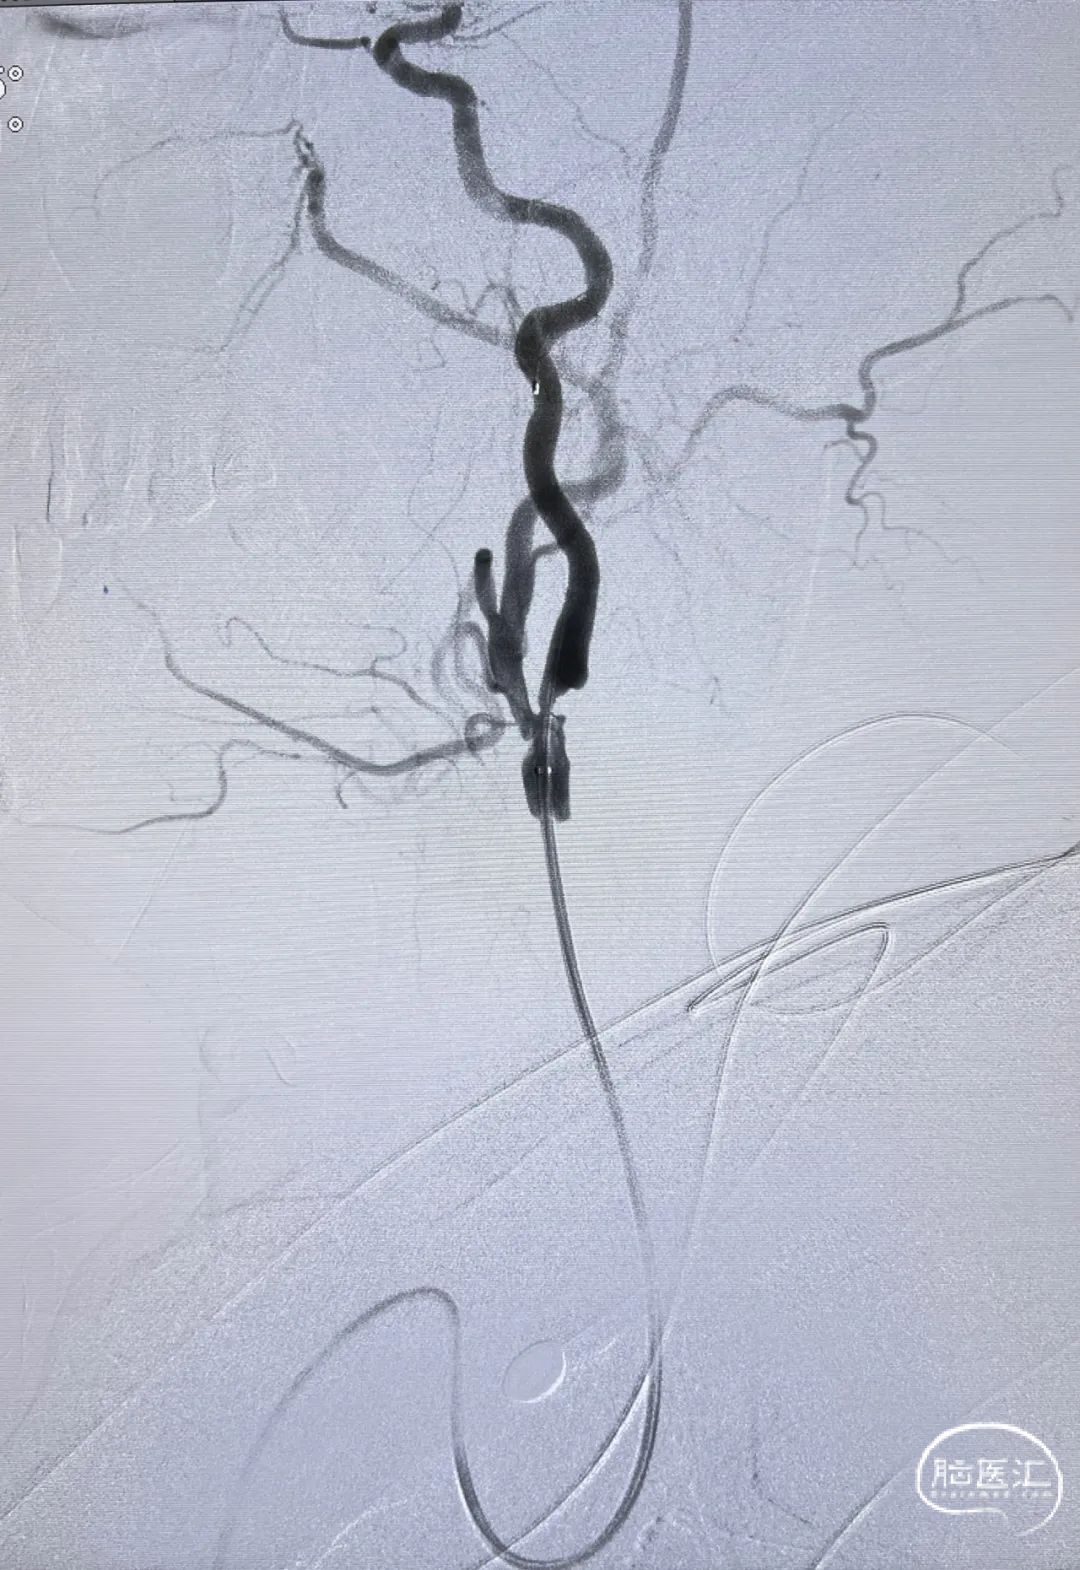

通路建立:经右侧桡动脉近桡穿刺,在赛诺APEX TRA GC™ SIM2-130cm内管的指引下将赛诺APEX TRA™ 6F 95cm经桡远端通路导引导管送行到颈总动脉末端。

5mm保护伞顺利到位,系统稳定。

5×30mm 扩张球囊到位,球囊扩张过程系统稳定。

通路弓上系统稳定支撑, 8×40mm Precise自膨支架顺滑到位。

支架系统释放过程,系统稳定。

左侧颈内动脉正侧位造影,狭窄解除。